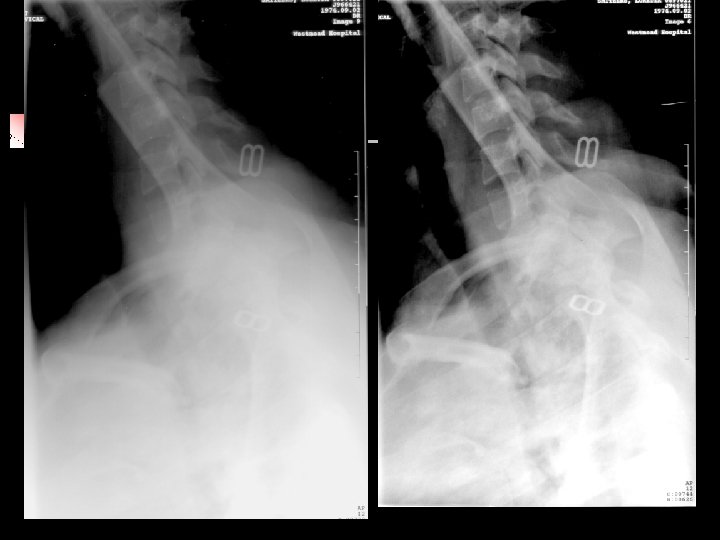

• Towel that was used to help in positioning a child NEW IMAGE • CR is MORE sensitive to • ARTIFACTS 110

CR image – n NEW IMAGE Line caused from dirt collected in a CR Reader 111